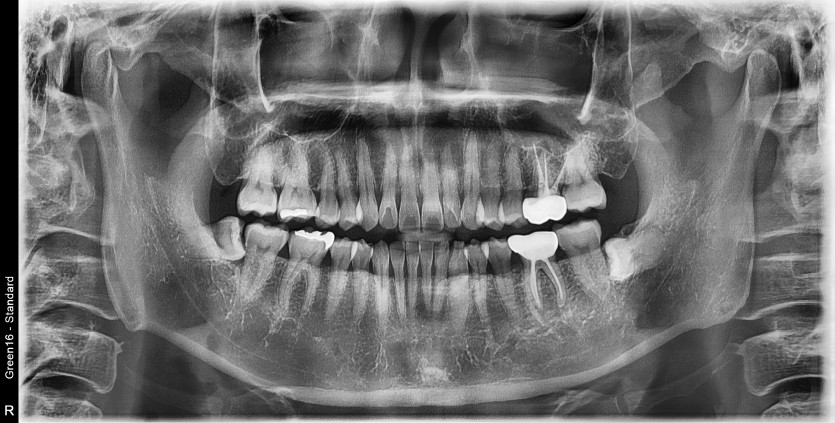

#48 사랑니 발치

구강 외과 전문의가 당일 발치했습니다.